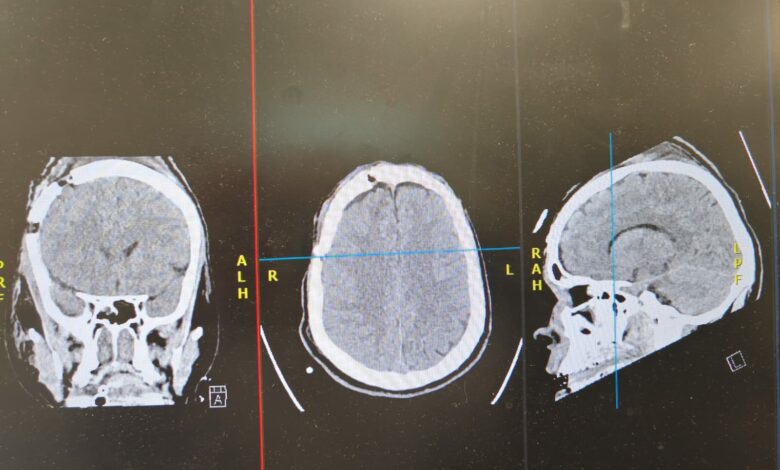

وبيّن التجمع على الفور تم وُضع المستفيد على جهاز التنفس الصناعي، وأُجريت له الفحوصات الطبية والأشعة اللازمة، والتي كشفت عن وجود نزيف حاد فوق الأم الجافية في الجهة الأمامية الصدغية اليمنى، تسبب في انزياح المخ، إلى جانب كسور متعددة في الجمجمة ممتدة من أعلى الرأس حتى مقدمته والجيوب الأنفية، وكسور في العظام المحيطة بحجاج العين، بالإضافة إلى كسر في الفقرتين العنقيتين السادسة والسابعة.

وأضاف تجمع المدينة أنه فور تشخيص الحالة جرى تجهيز غرفة العمليات بشكل عاجل، ونُقل المستفيد لإجراء عملية جراحية طارئة لإنقاذ حياته، تم خلالها فتح الجمجمة وتفريغ النزيف من الجهة الأمامية الصدغية اليمنى وصولًا إلى قاع الجمجمة خلف العين اليمنى. واستغرقت العملية ساعتين، تكللت – بفضل الله – بالنجاح مع السيطرة الكاملة على النزيف.